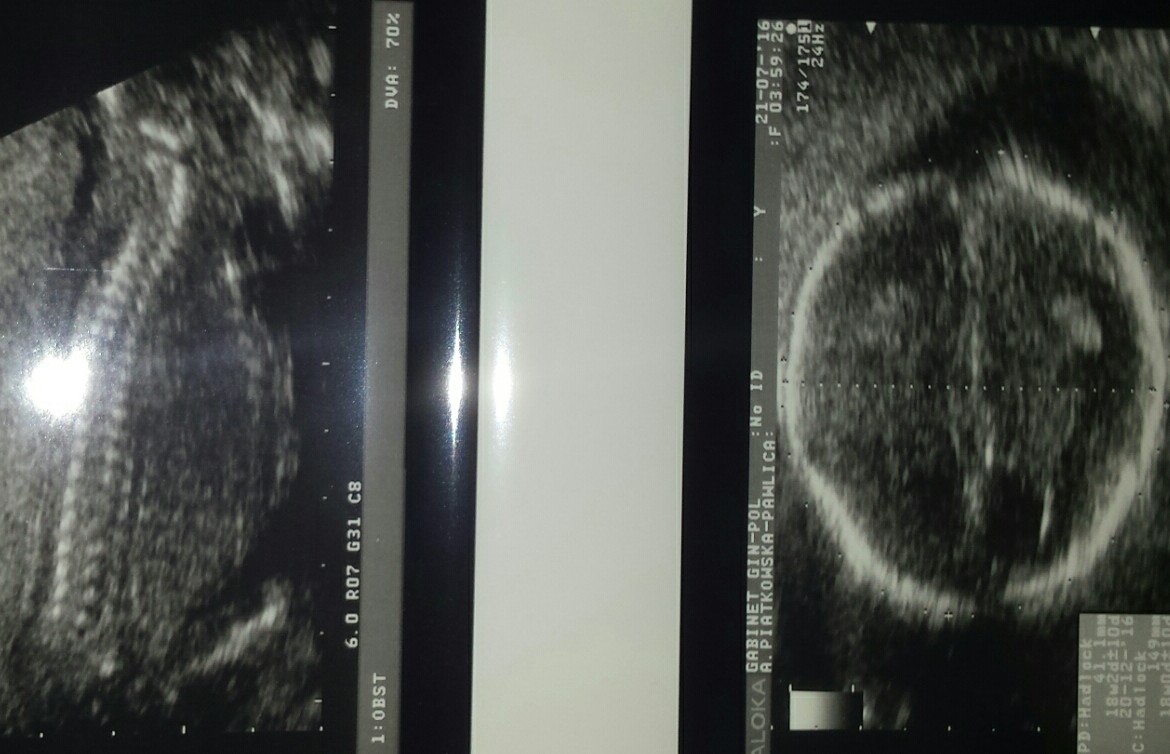

Oto obiecane zdjecia :)

Jest główka i ten nasz siusiak :) hihi. Mam filmiki nagrane z USG na płytce i na jednym otwieral i zamykał buźkę a na końcu język pokazał :D:D:D